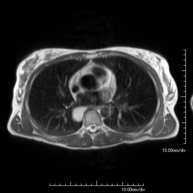

Prova diagnòstica no invasiva que consisteix en l'obtenció d'imatges d'alta definició anatòmica del tòrax mitjançant l'ús d'un camp electromagnètic i ones de ràdio (amb un emissor i un receptor). No utilitza radiació ionitzant. Està indicada en aquelles lesions pulmonars en les quals s'ha de descartar si hi ha infiltració del mediastí o de la paret toràcica, per diferenciar si una lesió toràcica és sòlida o quística, etc. En alguns casos caldrà emprar contrast paramagnètic (Gadolini) per completar l'estudi. - RM de Paret Toràcica